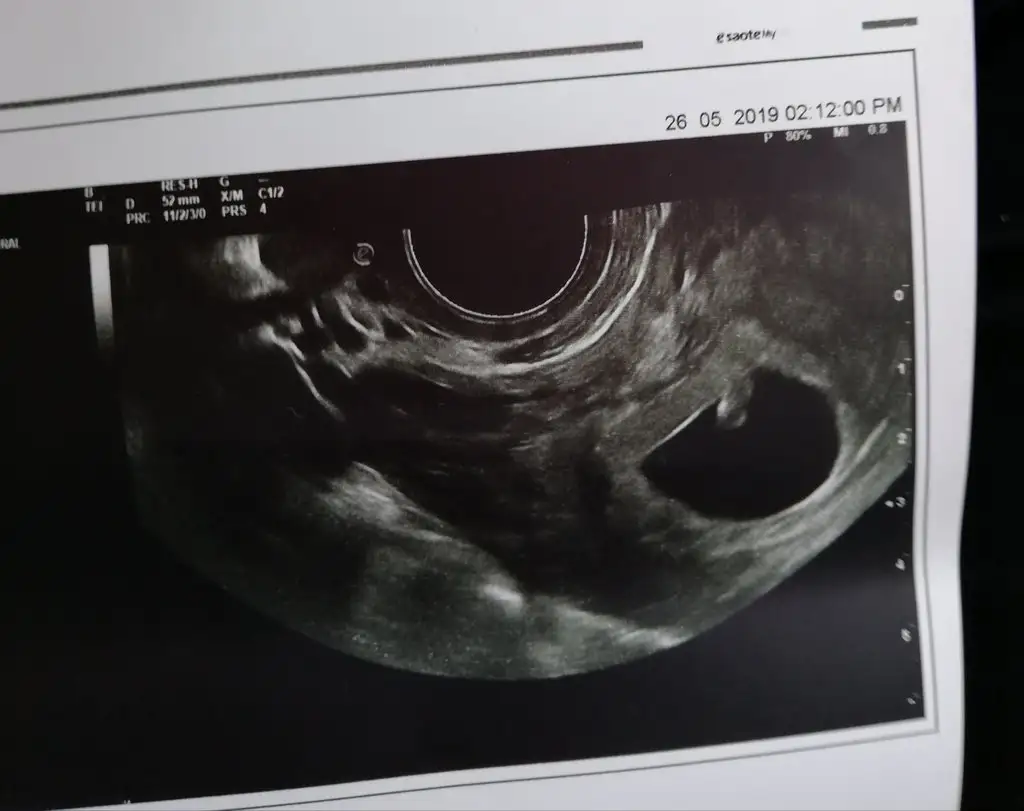

Canim banada yorum yaparmisin karindan usgRamzi teorisine göre ( bilimsel bir araştırma sonucuymuş ve %85 doğruluğu varmış). İlk 6-8 haftalık ultrason görüntüsüne göre bebeğin kesenin içersinde soldan ya da sağdan girişine göre cinsiyet tahmini yapılıyor. Bilimsel olunca tecrübeli annelerimiz yada anne adaylarımızdan yardım istiyoruz. Doğruluğu var mı öğrenmek adına :) Bizleri aydınlatırsanız çok seviniriz. bu teorieye göre;

Vajinal muayeneyle bakıldıysa eğer;

Sağdan girmiş gözüküyosa aslında solmuş ve ERKEK,

Soldan girmiş gözüküyosa aslında sağmış ve KIZ ,

Karından bakıldıysa eğer,

Soldan girmiş gözüküyosa gerçektede solmuş ve ERKEK,

Sağdan girmiş gözüküyosa gerçekte de sağmış ve KIZ,

Canım seninki karından ultrason sa solda erkek oluyor bu teori şuan etrafımdaki hamilelerde tuttu arkdaşımın sağdaydı kızı olacağını öğrendi dün bir tanıdıgımızın da soldaydı onada doktor yüzde yüz oğlan demiş ablamında oğlu olacak onun ultrason fotograflarına baktık onunki de soldaCanim banada yorum yaparmisin karindan usg